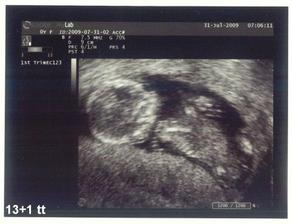

♥ 31.7.2009 6:50 - UTZ ve 13tt. ► Prcek se krásně rochnil v pupíku, má už 7cm, šíjové projasnění je v pořádku (0,8mm) a datum porodu přesně stanoven na 3.2.2010, váha 63,8kg.